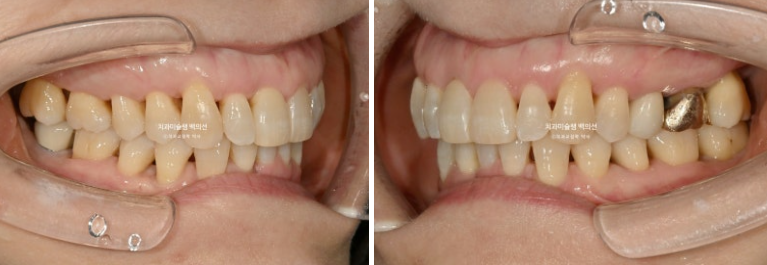

이제 전 후 비교 보겠습니다.

24.09~25.09

배열은 아주 깔끔합니다.

약해진 잇몸으로 인해 솟아나온 앞니 때문에 편하게 안 다물리던 입술이 비로소 편하게 다물리는 것 역시 기능적으로 큰 개선입니다.